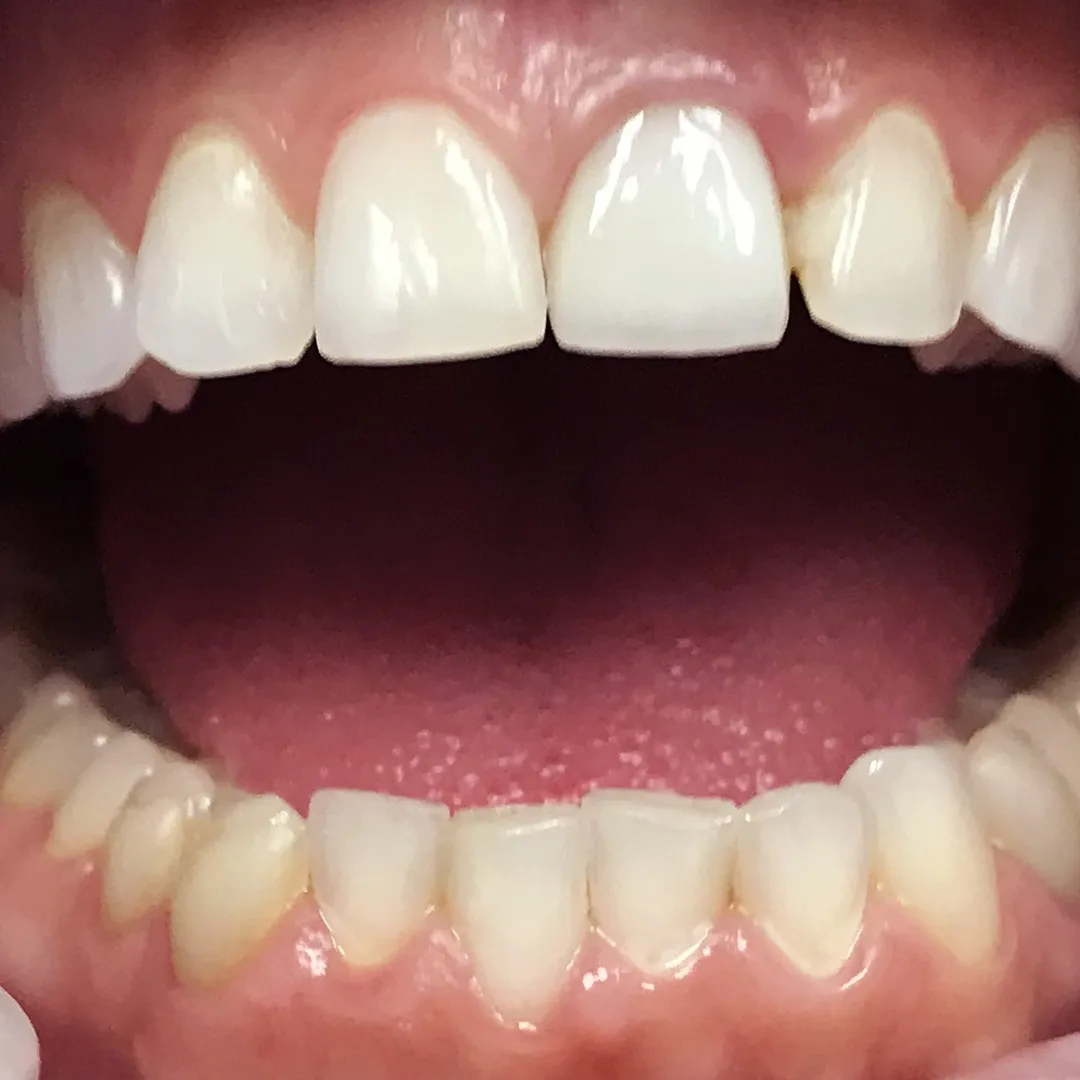

Повышение эстетических показателей путём установки циркониевой коронкиСмотреть работуСрок лечения:2 недели (в 2 этапа)Сумма лечения:35 000 руб.